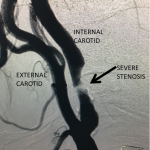

Figure 1.

This 77-year-old man with a history of stroke in 2013 presented to a small community hospital with aphasia upon awakening. Given the unclear timing of onset of his symptoms he was not deemed a candidate for intravenous thrombolytic. His NIHSS was 2 in the emergency room. He was admitted to the hospital where a CT (Figure 1) and CTA were performed showing a left frontal small infarct and severe extracranial carotid stenosis on the left. MRI could not be performed because of the patient’s pacemaker. Examination was significant for an awake gentleman with normal cranial nerve function and normal motor exam but significant expressive aphasia. Receptive aphasia was intact. He was placed on Aspirin.

Catheter angiography prior to angioplasty revealed critical stenosis (Figure 2). Angioplasty was therefore performed under local anesthesia with an embolic protection device deployed to catch any dislodged debris (Figure 3). After angioplasty, a stent was opened across the lesion to maintain long-term patency (Figure 4). Post-stent angiography showed smooth dilatation of the lesion. The patient’s aphasia continued to improve at his 6-week follow-up visit and duplex revealed no significant stenosis through the stent.